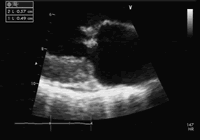

行冠状动脉造影发现:左前降支中远端局限性狭窄,约70%,左回旋支、右冠状动脉未见狭窄及斑块。超声心动图(UCG,图1):二尖瓣脱垂,轻度二尖瓣关闭不全,二尖瓣前叶赘生物4.9 mm×5.7 mm;节段性室壁运动异常(左室间隔下段,心尖部)。